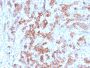

Positive Control

PC3, BT474, HepG2, HDLM-2 or Daudi cells. Tonsil, lymph node or spleen.

IHC, FFPE (verified)

IHC (FFPE) (verified)